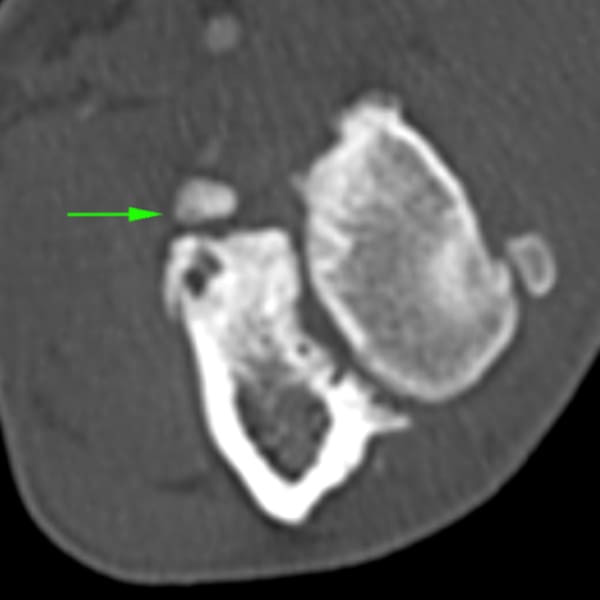

La Tomografía computerizada (CT) o TAC es la técnica por imagen de elección. El procesado avanzado de la imagen nos permitirá visualizar finos cortes de la anatomía y detectar pequeñas lesiones (por ejemplo, fragmentación del proceso coronoides), las cuales son difíciles de diagnosticar en radiografías convencionales.

• Enfermedad del proceso coronoides medial (EPCM): se trata de la condición más encontrada de todas las que se incluyen en la displasia de codo. El proceso coronoides puede encontrarse malformado, fisurado e incluso fragmentado. Como resultado de esta enfermedad y del roce anormal de dicha estructura con la superficie articular del cóndilo humeral medial, se produce un desgaste acelerado de las superficies cartilaginosas del aspecto medial del codo dando lugar al Síndrome del compartimento medial, el cual se ve favorecido por la sobrecarga que soporta la región interna de la articulación en condiciones fisiológicas.